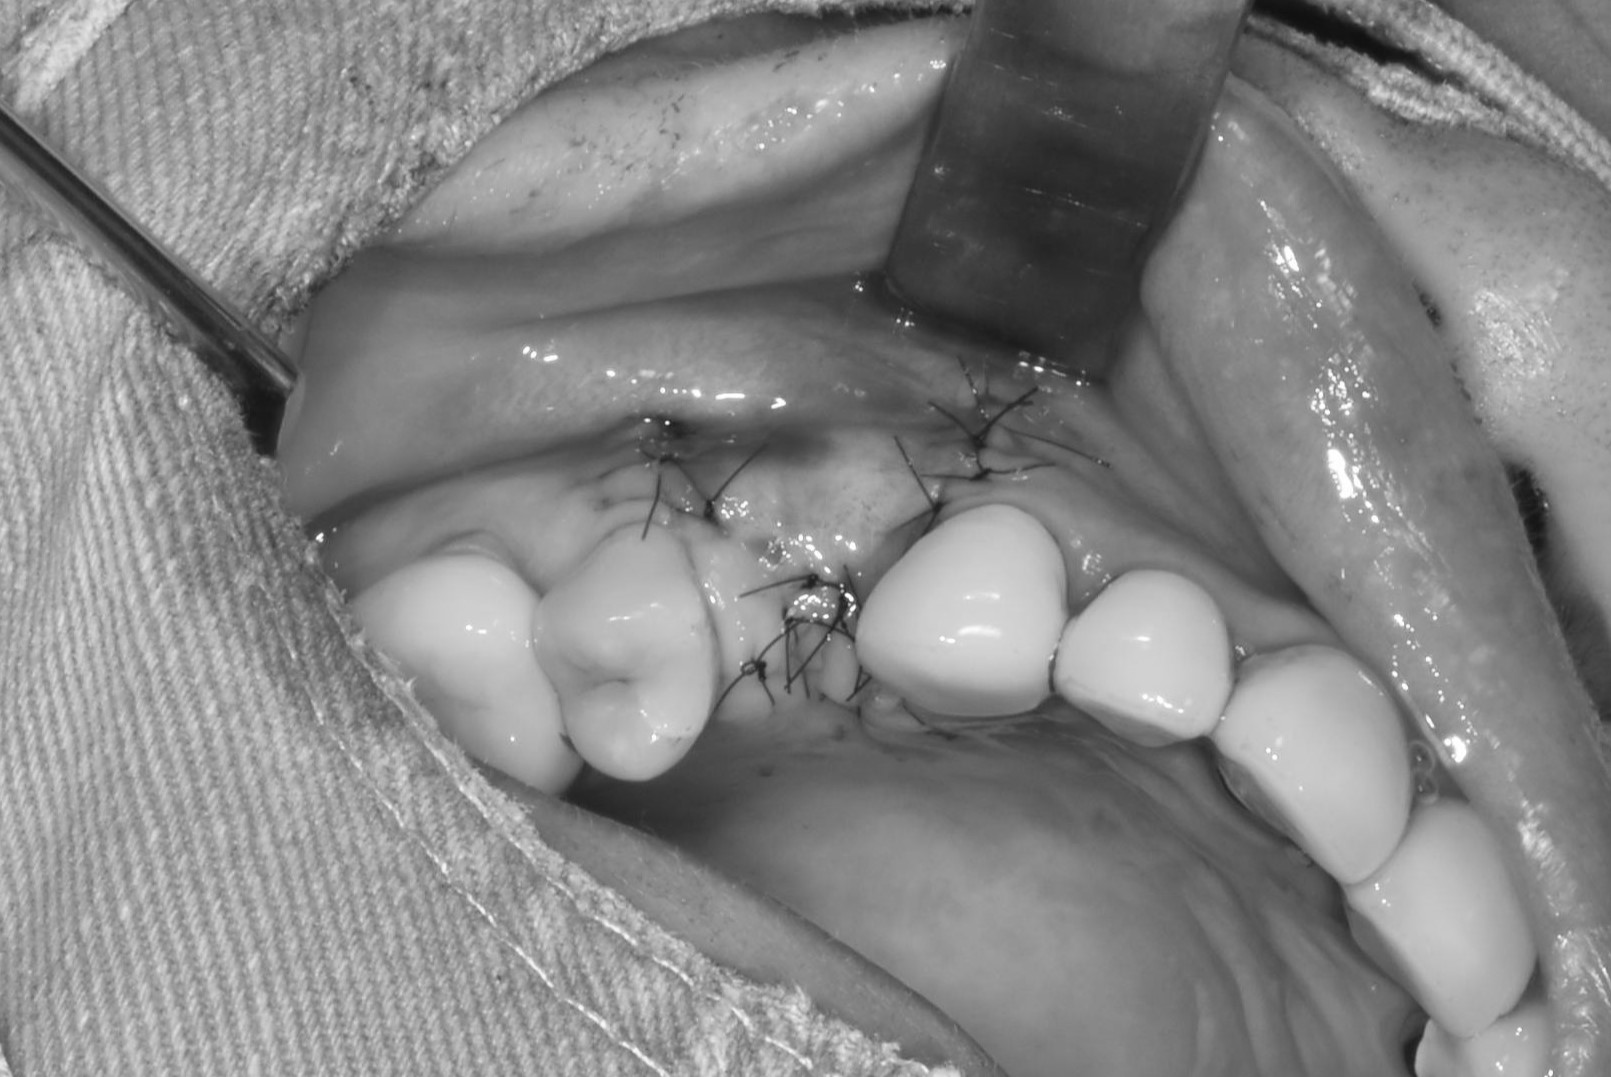

翻瓣補骨的區域

補入所需的骨粉

完成後縫合,等待傷口癒合

每個人骨頭恢復所需不同,需定期回診給醫生評估是否進行下一個階段